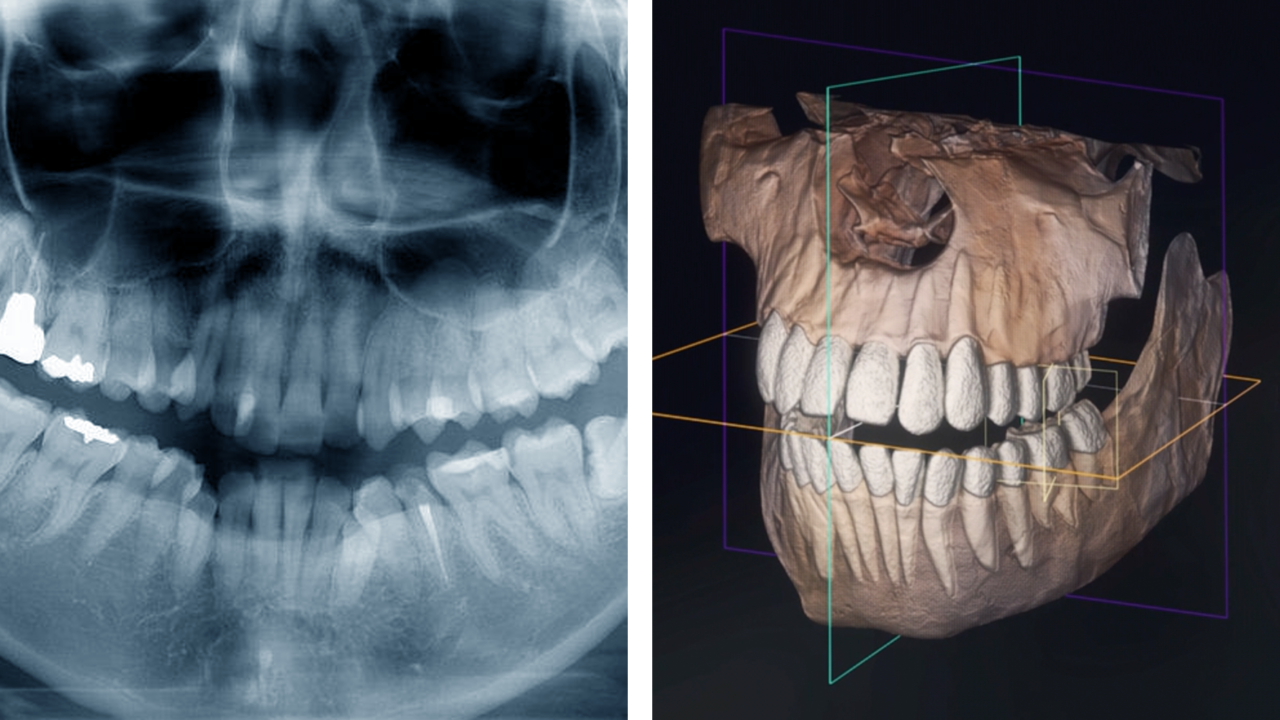

歯科用CTで検査してくれるか

院内に歯科用CTのない経験不足の歯科医師は、レントゲンの撮影だけで済ましてしまいがち。

CT撮影を行わずに治療を進めるケースが少なくありませんが、これが矯正治療に失敗する理由の一つ。

当院含め、矯正を専門に手がける経験豊富な歯科医師は、歯科用CTでの3次元診断を行います。

2次元レントゲンではわからない、骨の厚みや顎の幅、歯根の正確な長さ、顎関節の形状を三次元で見ながら診断することで、より安全で正確な治療計画を立てられるのです。